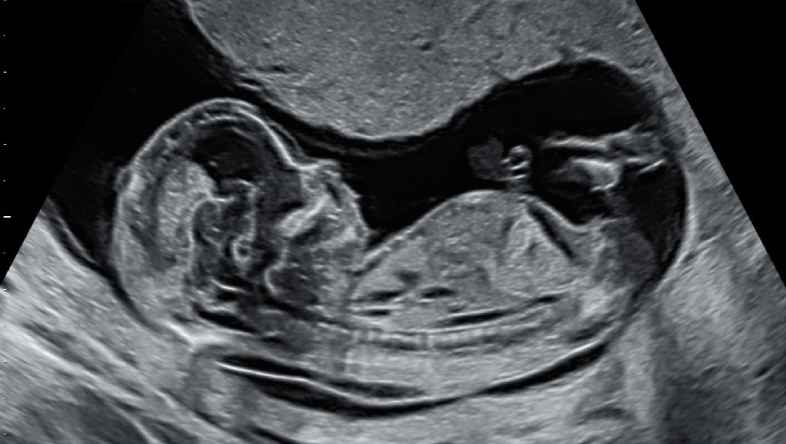

Nếp gấp da gáy (nuchal translucency) là một lớp dịch tích tụ ở phía sau cổ của thai nhi. Đo nếp gấp da gáy là một phần của xét nghiệm siêu âm thai kỳ, thường được thực hiện trong thai kỳ. Kết quả của đo nếp gấp da gáy có thể giúp phát hiện các dấu hiệu bất thường về nhiễm sắc thể hoặc các dị tật bẩm sinh ở thai nhi.

Phương pháp siêu âm được sử dụng để thực hiện đo nếp gấp da gáy. Đây là quy trình không xâm lấn và an toàn cho cả mẹ và bé. Trong quá trình siêu âm, bác sĩ sẽ sử dụng máy siêu âm để đo khoảng cách giữa da và mô mềm ở phía sau cổ của thai nhi. Quy trình này thường chỉ kéo dài từ 20 đến 40 phút.

Khi đo nếp gấp da gáy của thai nhi, chỉ số được coi là bình thường nếu nằm dưới 3,5mm và chiều dài của thai nhi từ 45mm đến 84mm. Chỉ số này giúp bác sĩ đánh giá nguy cơ mắc các bất thường nhiễm sắc thể của thai nhi.

Chỉ số nếp gấp da gáy sẽ thay đổi theo tuổi thai của em bé. Ví dụ, ở tuần thai thứ 11, chỉ số tiêu chuẩn là khoảng 2mm, trong khi ở tuần thai thứ 13, chỉ số này là khoảng 2,8mm. Sự khác biệt này phản ánh sự phát triển bình thường của thai nhi.